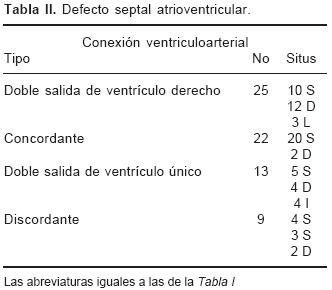

En los setenta corazones estudiados el situs atrial que predominó fue el solitus seguido de dextroisomerismo, inversus y levoisomerismo (Figs. 2A y 2B). La conexión A–V predominante fue concordante seguida de la doble entrada a ventrículo único, doble entrada a ventrículo derecho, ambigua y discordante (Tabla I). Los tipos de conexión ventriculoarterial se consignan en la Tabla II.